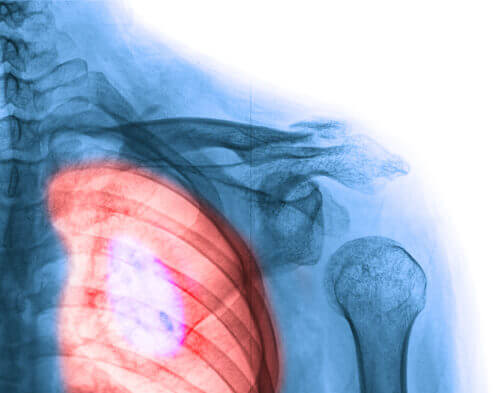

1.Meme Kanseri

Şüphe yok ki kadınlar üzerinde en büyük etkiye sahip kanser türü meme kanseridir. Ama burada belirtmemiz gereken bir şey daha var ki o da en yüksek hayatta kalma oranına sahip kanser türünün de meme kanseri olduğudur.

Sizin de meme kanserine yakalanmış bir tanıdığınız olması muhtemel, belki de bir sevdiğinizi bu hastalığa kaybettiniz. Ancak, gün geçtikçe bilim ilerliyor ve daha fazla kadın bu hastalığı yeniyor. Bu durumda erken teşhis için kendi kendinize yapacağınızı meme muayeneleri ve çektireceğiniz mamografiler büyük önem taşımakta. Aklınızda bulunmasında fayda olan bazı belirtiler şunlar: